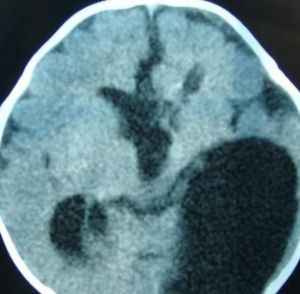

1.CT表現:

表皮樣囊腫(2)有兩種形態:

①扁平型:形態不規則,腫瘤沿蛛網下腔蔓延,“見縫就鑽”為其特點。

②團塊型:多位於硬膜外,呈球形,為混雜密度。

(3)腫瘤可有鈣化,但不常見,多位於囊壁上,亦可在囊內。

(4)腦橋小腦角池、環池、四疊體池的腫瘤可致腦幹受壓、變形;

(5)增強掃描時病灶不強化,偶見邊緣輕度弧形增強。